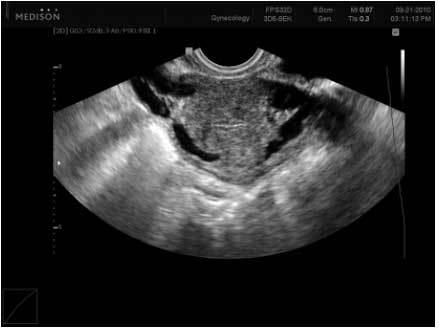

Флеболог после осмотра рекомендует больному пройти необходимые исследования. Это – УЗИ вен и сосудов нижних конечностей, доплеровское обследование (по показаниям), сдача общих анализов. По результатам анализов врач ставит диагноз и решает вопрос о лечении.

- УЗИ сосудов с доплерографией.

Он проводит ультразвуковое обследование, данные которого прилагаются к визуальному осмотру состояния сосудов, опросу жалоб пациента, выяснению образа жизни, имеющихся болезнях, включая наследственные.

- Инструментальная диагностика (УЗИ сосудов; высокоточный метод исследования венозного кровотока; рентген после введения в вену специального вещества; определение внутривенного давления и т.п.).